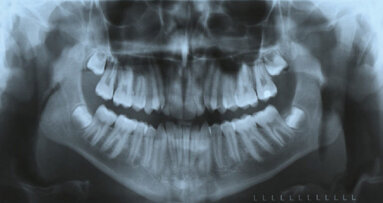

Fig. 15: Occlusion with the mandible in centric relation and a significant open bite.

Fig. 16: Occlusion with intercuspation but a non-functional

mandibular position.